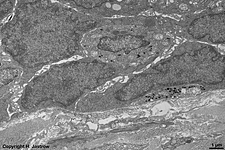

Lamina propria mucosae with

connective tissue cells (rat)

idem (rat) 2 plasma cells in the

Lamina propria mucosae (rat)

detail: plasma cell (rat)

--> furter details

other plasma cell of the

Tela submucosa (rat)

Schwann cell of the

Plexus submucosus (rat)

The colon (Terminologia histologica: Colon) is characterised by exclusively crypts and a large diameter. Its wall is similar to gut in general but has some specialities. The mucosa has a superficial Lamina epithelialis bordering the lumen with vast amounts of goblet cells, enterocytes and a few enteroendocrine cells at the base of the crypts. The underlying loose connective tissue layer is called Lamina propria mucosae. It shows very large aggregations of secondary lymph follicles that join each other (Folliculi lymphatici aggregati = Payer's plaques), that may reach down in further layers. A thin layer of smooth muscle cells (Lamina muscularis mucosae) is the deepest layer of the mucosa. The following Tela submucosa is a thicker layer of loose connective tissue which shows the submucous nerve plexus (Plexus submucosus; Meissner's plexus) and extends to the following Tunica muscularis. The latter has a circular layer (Stratum circulare) which is very thin in the area of haustres and a logitudinal layer (Stratum longitudinale) which is only evident in the region of taenia. In between these two smooth muscle cell layers the Plexus myentericus (Auerbach-Plexus, a further autonomous nerve plexus of the gut) is encountered. The outermost layer Tunica serosa is a small loose connective tissue layer (Tela subserosa) covered with the monolayered squamous epithelium of the peritoneum only in areas where the colon lies intraperitoneally (e.g., transverse and sigmoid portion). In other (retroperitoneal) regions an adventitia formed by connective tissue anchors the colon to neighbouring structures.